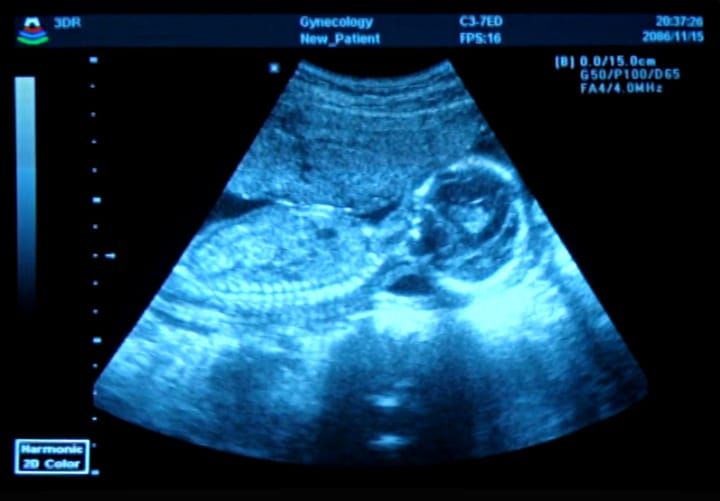

Kicking in the womb might be uncomfortable for the mother, but can have benefits for the foetus' joints.

I am not a mother myself, but I imagine having a tiny human kicking and moving around in your womb can feel quite uncomfortable. At some point, you may, out of frustration, wonder: why do they move around so much?! A research group co-led by Paula Murphy from Trinity College Dublin has been able to provide the answer: to develop the joints. Based on observing clinical conditions where movement is restricted or limited, scientists postulate that movement and mechanical forces are required for joint development and maintenance in adults. However, little is known about the molecular details of how this works. This group in Dublin is the first to identify key pathways involved in the mechanosensing aspect of joint development.